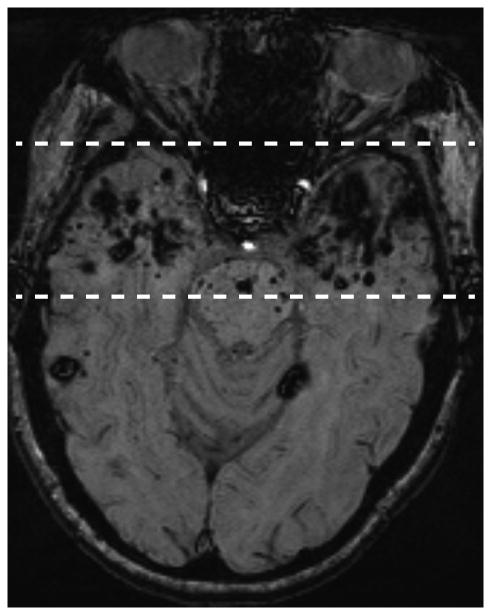

Patient 2 is a 49 year old woman who was treated with radiation therapy in 1989 for a nasopharyngeal carcinoma (radiation estimated at 70 Gy for the temporal lobes and 50 Gy for the cerebellum, both fractionated). Although CCMs are present throughout the brain, there is a high burden in the radiated temporal lobes and the inferior cerebellum, included in treatment of upper neck lymph nodes (Figure 2).

Figure 2.

A (left) and B (right): Axial MRI susceptibility-weighted images. Nasopharyngeal carcinoma treatment resulted in bilateral temporal lobe exposure to therapeutic doses of radiation (estimated 70 Gy). Note the much higher density of CCM lesions (both large and small) in the temporal lobes (dashed lines) compared to the remaining brain (A). The cerebellum was also exposed to therapeutic radiation (estimated 50 Gy) and likewise has a heavy CCM burden (B).